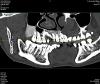

docseamew Опубликовано 6 сентября, 2013 Автор Поделиться Опубликовано 6 сентября, 2013 Уважаемые коллеги, прошу Вашей помощи еще раз. Я особо удачливый пациент, помимо вышеозначенной проблемы (стараюсь делать все как Вы посоветовали, но пока все в том же состоянии, но хоть перифокального воспаления нет), у меня есть еще вот какая беда. Одновременно с "удачным" лечением, у меня диагностирована опухоль альвеолярного отростка ВЧ. Локализуется в районе 18 удаленного зуба, размер около 20 на 24 мм, прилегает к пазухе и слегка заходит на корни 16-17 зубов. Предположительно может быть фиброзной дисплазией или еще чем похуже. Проблема у меня такая: 27 августа у меня в минском отдЧЛХ под местной анестезией взяли биопсию - просто фрезой выпилили трубчатый кусочек кости. Слизистую не резали и не ушивали, дефект затампонировали гемостатической губкой. Отправили домой и сказали мазать 3 раза в день зеленкой, обещали что через дней 10 закроется. Но не похоже, чтоб оно закрывалось. Через 3 дня отошел мацерированный кольцевидный кусочек (первоначальной отверстие было около 4 мм в диаметре. Теперь дефект слизистой составляет около 10 мм на 8 мм, несколько воспаленный край. В центре видно белое (кость с фибрином?) плюс видно трепанационное отверстие. Болевые ощущения умеренные, в основном при раздражении пищей. Скажите пожалуйста, это может закрыться? И что лучше использовать, если лечение дефекта консервативное? Ссылка на комментарий

docseamew Опубликовано 6 сентября, 2013 Автор Поделиться Опубликовано 6 сентября, 2013 Vot esche CT est u menya Ссылка на комментарий

docseamew Опубликовано 6 сентября, 2013 Автор Поделиться Опубликовано 6 сентября, 2013 vtoroi scan Ссылка на комментарий

docseamew Опубликовано 6 сентября, 2013 Автор Поделиться Опубликовано 6 сентября, 2013 i tretij scan Ссылка на комментарий

docseamew Опубликовано 6 сентября, 2013 Автор Поделиться Опубликовано 6 сентября, 2013 Извините за транслит, нет на том компьютере русской клавиатуры, и юзер я еще тот. Что с психиатра возьмешь - артист разговорного жанра...Было бы интересно узнать Ваше мнение, уважаемые коллеги, на что это похоже? А то как-то сиротливо ждать биопсии, да еще фрезевое отверстие не заживает...Заранее спасибо. Ссылка на комментарий

docseamew Опубликовано 6 сентября, 2013 Автор Поделиться Опубликовано 6 сентября, 2013 Каких-то клинических проявлений не было, никто не обращал внимания на опухоль. 18 зуб располагался практически горизонтально и был удален 2 года назад после развития пульпита. Удалился очень легко. Слизистая над опухолью была не измененная (до биопсии). Вот такой анамнез. Ссылка на комментарий